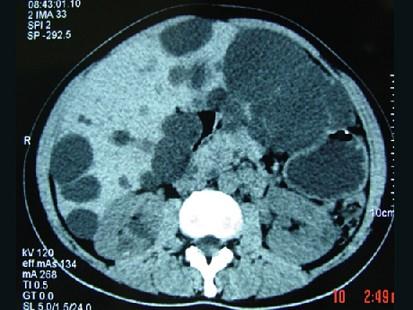

问题 女,20岁,右上腹胀,影像表现如图,最可能的诊断是 ( )

选项 A、肝脓肿并肾囊肿 B、多发性肝囊肿并多发性肾囊肿 C、多囊肝并肾多发囊肿 D、肝淋巴管瘤并多发性肾囊肿 E、先天性肝内胆管扩张并多囊肾

答案 C